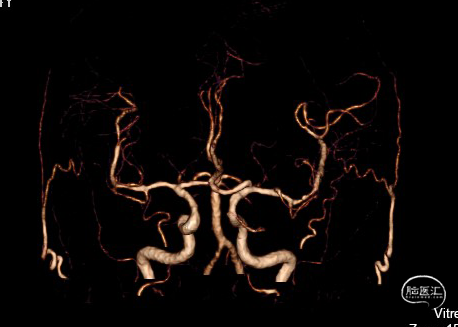

现病史:患者2024.6.6 15:00突发言语不利伴右侧肢体活动障碍,17:00就诊于急诊神经内科,行头颅CT未见出血,立即予以静脉溶栓治疗后症状未缓解。完善头颅CTP提示左侧大脑中动脉M2段狭窄,为责任血管,存在低灌注区,附见一动脉瘤。

DSA检查提示左侧大脑中动脉上干闭塞

扩张后血管依然闭塞,改用2.0*15mm 球囊,扩张后提示M2段血流通畅,可见动脉瘤大小约4-5mm。

为尽快开通血管及处理动脉瘤,选择2.75*20mm 密网支架释放,并予以2.0*15mm 球囊后扩。

该病例血管开通后可见动脉瘤,考虑患者已行静脉溶栓,并且术后需要长时间应用抗血小板药物治疗,动脉瘤存在破裂风险;故选用血流导向装置对动脉瘤瘤颈进行覆盖,减少血流对动脉瘤的冲击进而降低破裂风险,同时兼顾闭塞开通与动脉瘤治疗。